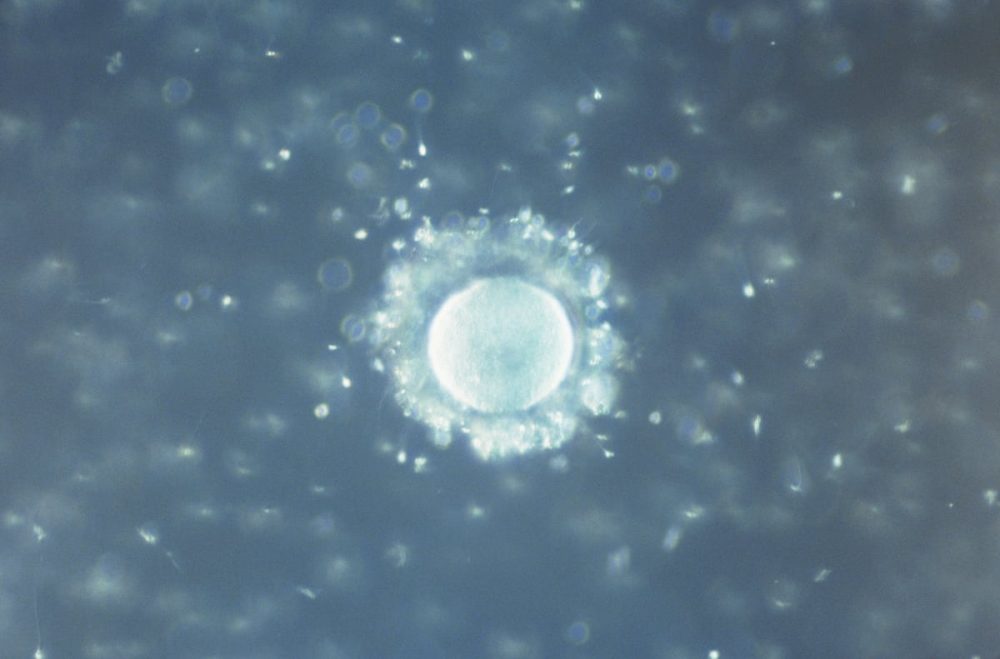

科学界近日传来震撼发现——研究人员竟在人类精液与卵泡液中检测到微塑料,进一步引发全球对生殖健康的担忧。

这项由西班牙团队进行的研究,在巴黎举行的第41届欧洲人类生殖与胚胎学会年会上公布。研究人员对25名女性的卵泡液进行分析,结果显示有69%含有微塑料;在18名男性的精液样本中,也有55%检测呈阳性。

卵泡液是包围卵子的关键环境,而精液则与男性生育能力直接相关,在这两种重要的生殖液体中发现微塑料,意味着这些微小颗粒已能渗入人体最敏感的生殖系统区域。

美国新墨西哥大学教授坎彭指出,这项发现再次证实微塑料能进入血液,并透过循环系统抵达卵巢与睾丸,但到底微塑料如何穿越人体屏障,科学界至今仍无法完全解释。